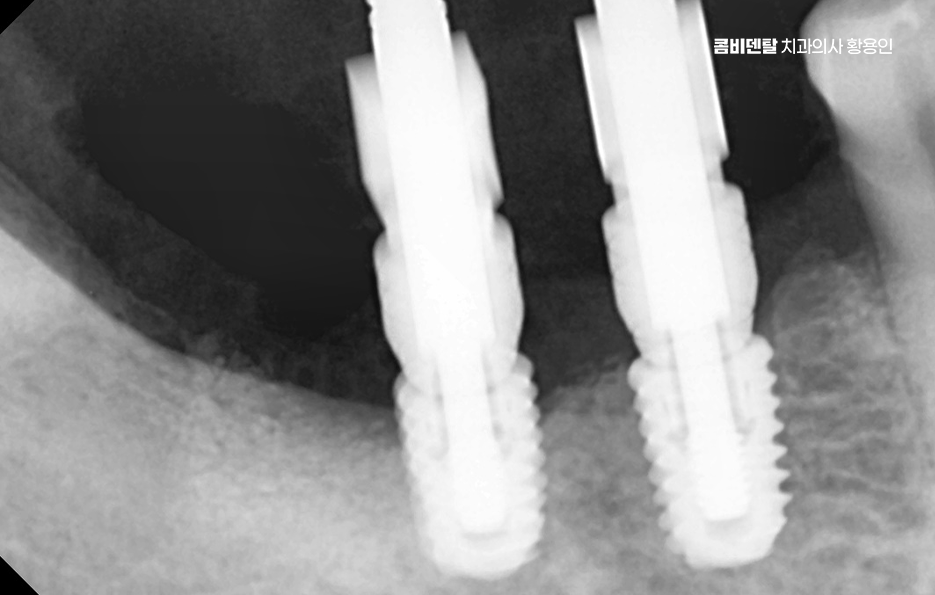

임플란트 치료의 주된 원리는 '골유착'에 있는데 이 단어가 조금 생소할 수 있지만 쉽게 말하면 임플란트의 인공치근, 자연치의 뿌리 역할을 대신하는 인공치근은 티타늄 재질로 구성되어 있고 잇몸뼈 안에 심으며 그 뼈가 이 인공치근을 자기 뼈처럼 감싸서 단단하게 붙는 현상을 말하는 거예요

티타늄은 인체에 생물학적으로 안정적인 금속이라서 뼈가 이물질로 인식하지 않고 잘 달라붙는 성질이 있는 것으로 치조골 안에 이 티타늄으로 구성된 인공치근이 수개월 동안 안정적으로 뼈와 결합되는 과정을 거치게 되면서 자연치아에 버금가는 저작력을 갖추게 되는 것이 주된 치료 원리라고 할 수 있었어요